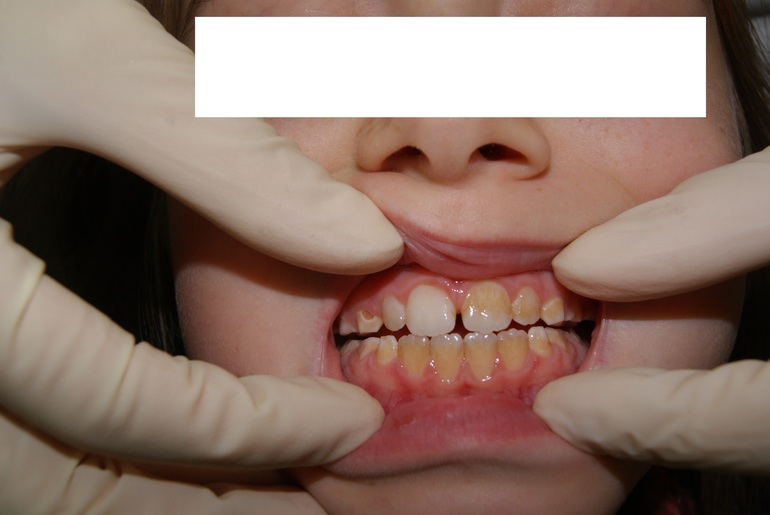

Налет на зубах

Детские зубные проблемы

Прием антибиотиков, полоскание полости рта растительными антисептиками, отсутвие гигиены полости рта и ВУАЛЯ - желтые шершавые зубы. (зубик левее по центру мы уже почистили)

Через 20 минут адаптации (девочка очень сильно боялась всего, пришлось потрудиться, чтобы завоевать доверие) и 20 минут чистки у нее стали беленькие зубки!!!

Да, бывает связь з ЖКТ. Но тут было именно использование в полоскании горла отвара ромашки и зверобоя + девочка сама призналась, что долго не чистила зубы... Вот образовался плотный налет и пропитался растительными полоскалками